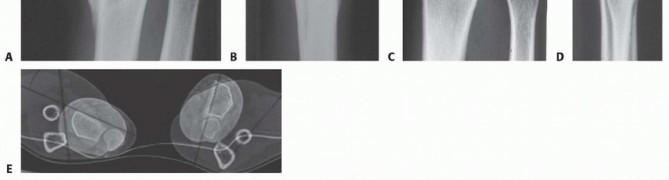

Distal radius malunion is best defined as malalignment associated with dysfunction. Malalignment does not always result in dysfunction. In particular, the vast majority of older, low-demand patients function very well with deformity. Dysfunction can include loss of motion, loss of strength, or pain. 1, 2, 5 Pain can be the most difficult to associate with deformity. Osteotomy for pain—as with any surgery for pain —is relatively unpredictable and should be undertaken with caution. Carpal malalignment, ulnocarpal impaction, and distal radioulnar joint (DRUJ) malalignment are all potentially painful and can be variably addressed. The relationship between distal radius malunion and carpal tunnel syndrome is debated. Some surgeons claim a direct causal relationship as well as the ability to improve carpal tunnel syndrome with osteotomy alone. ## ANATOMY Loss of alignment can be measured on radiographs. Angulation of the articular surface on the lateral view is measured as the angle between a line connecting the dorsal and palmar lips of the distal radius articular surface on the lateral view and a line perpendicular to the radius shaft. Ulnarward inclination (often called radial inclination , a misnomer because the articular surface tilts toward the ulna) is measured as the angle between a line connecting the ulnar limit and the radial limit of the distal radius articular surface on the posteroanterior (PA) view and a line perpendicular to the radial shaft. Ulnar variance is a better measure of shortening of the radius than radial length. It is measured as the distance between two lines drawn perpendicular to the radial shaft on the PA view, one at the level of the most ulnar corner of the lunate facet and the other at the distal limit of the ulnar head. Positive ulnar variance means that the ulna is longer than the radius. Negative means the ulna is shorter. Loss of articular surface alignment can be measured on radiographs as gap, step, or subluxation. This is most accurately measured using computed tomography (CT) images ( FIG 1). Sources of variability in radiographic measurements include variation in the radiographs, imprecision in the measurement techniques, and imprecision in the selection of the points of reference. ## PATHOGENESIS Fractures of the distal radius heal rapidly. A malaligned healing fracture can be considered a malunion within 4 to 6 weeks of injury. Risk factors for fracture instability, loss of reduction, and malunion include age older than 60 years, more than 20 degrees of dorsal angulation, dorsal metaphyseal comminution, comminution extending to the volar metaphyseal cortex, associated fracture of the ulna, and displaced articular fracture. Risk factors for fracture instability include age, metaphyseal comminution, dorsal tilt, ulnar variance, and lack of functional independence. Manipulation of previously reduced fractures that redisplace in a cast or splint signifies instability and is not worthwhile. Limitations of various treatment techniques may contribute to creation of a malunion. Percutaneous pins alone may not be sufficient to maintain alignment when there is substantial metaphyseal comminution. External fixation alone without ancillary percutaneous pin fixation of the fracture

FIG 1 • The arc method for measuring articular malalignment of the distal radius. The distance between B and D is the articular step, and the distance between A and C is the maximum articular ga (After Catalano LW III, Cole RJ, Gelberman RH, et al. Displaced intra-articular fractures of the distal aspect of the radius: long-term results in young adults after open reduction and internal fixation. J Bone Joint Surg Am 1997;79[9]:1290-1302.) 143 Early removal of pins or an external fixator. Settling of the fracture can also be observed after implant removal more than 6 weeks after injury, particularly when there is substantial metaphyseal comminution. Nonlocked plates may loosen in osteopenic metaphyseal bone. Complacence must be avoided. Many older patients desire optimal wrist alignment and function, and treatment decisions should not be made on chronologic age alone. ## NATURAL HISTORY Ulnar-sided wrist pain can improve for a year or more after fracture of the distal radius, so patience is warranted. Lack of forearm rotation may be related to capsular contracture or bony malalignment. For slight malunions, patience with exercises and rehabilitation is advisable. Although it is often stated that an extra-articular distal radius malunion leads to future arthrosis, there are no data to support this contention. After a recovery period of 1 to 2 years from fracture, the functional deficits seem fairly stable. Articular incongruity or subluxation in relatively nonarticular areas can be reasonably well tolerated, but in most cases, intra-articular incongruity will lead to arthrosis, pain, and dysfunction. There is no clear time frame for these changes— indeed, symptoms do not correlate well with radiographic anatomy or arthrosis and the predictors of arthrosis are not well established. ## PATIENT HISTORY AND PHYSICAL FINDINGS Pain should be very discrete and specific. It is important that there be a direct correlation of the pain with a clear operative target. Vague, diffuse, or disproportionate pain should not be treated with osteotomy. Pain alone is not a good indication for osteotomy, so the interview should elicit specific aspects of the pain for which there is a good operative target and the risks of surgery are justified.